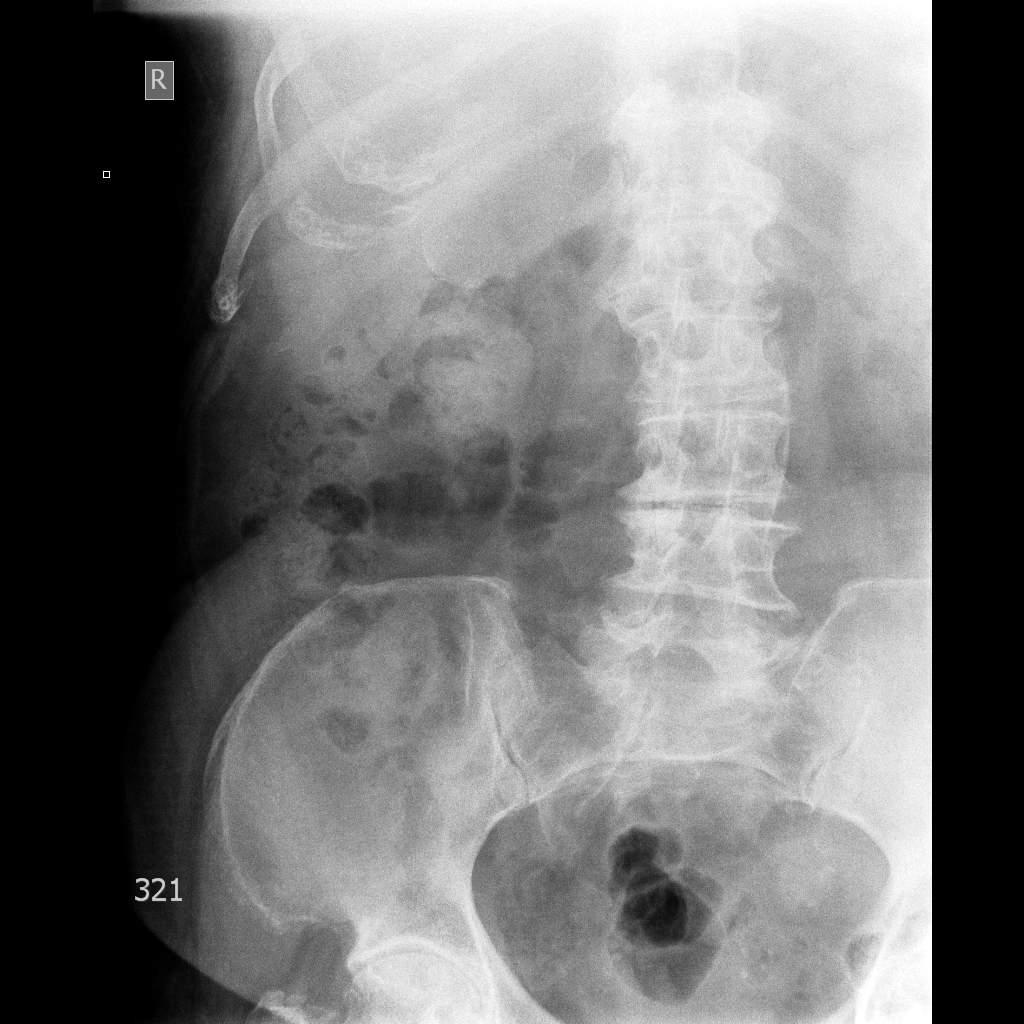

Фарфоровый желчный пузырь (Porcelain gallbladder)

Женщина средних лет без жалоб на здоровье.

Бабушка из отделения сестринского ухода, без жалоб на боли в животе. Лаб. анализы не изменены.

Pilvas-UROGRAMA AP-2014.04.18-09_10_09-687.JPEG